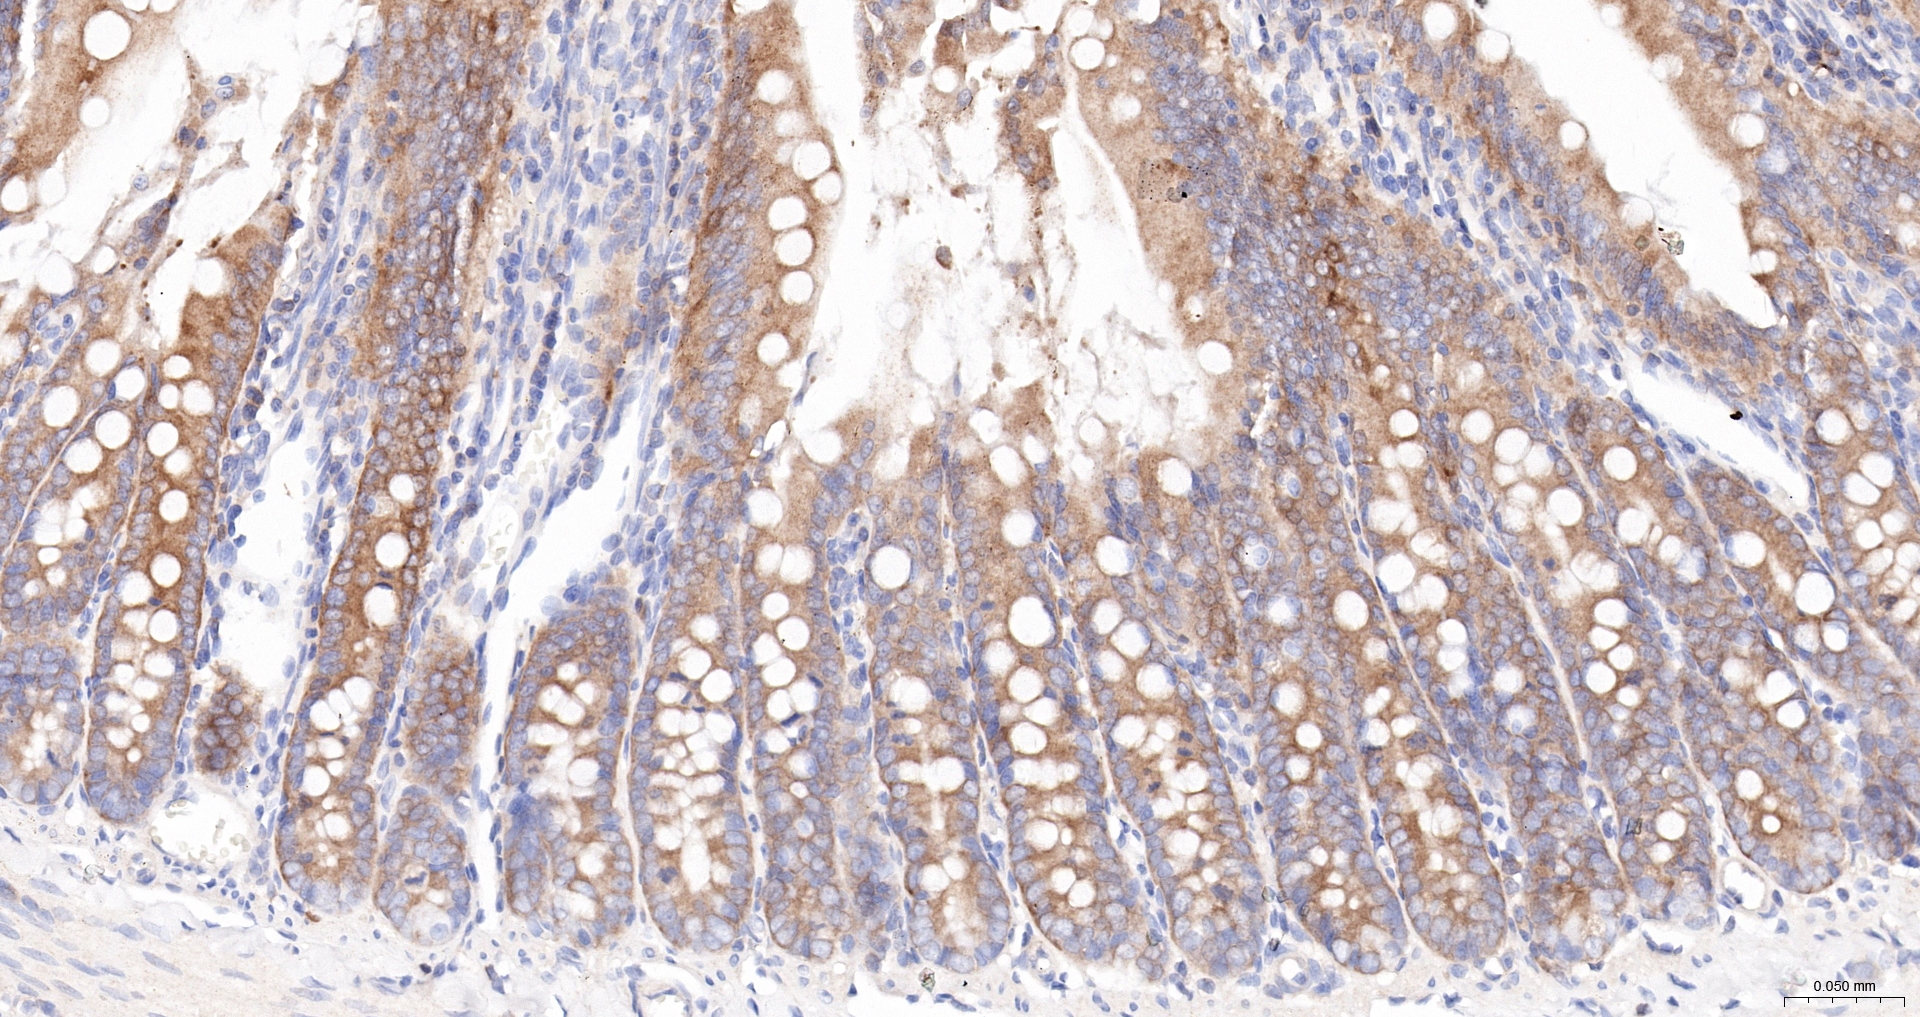

IHC-P IHC-P1:100-500

IHC-F IHC-F1:100-500